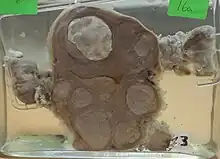

Multiple uterine leiomyoma

Multiple uterine leiomyoma Large subserosal fibroid

Large subserosal fibroid Multiple uterine leiomyoma with calcification

Multiple uterine leiomyoma with calcification

Fibroids may be single or multiple. Most fibroids start in the muscular wall of the uterus. With further growth, some lesions may develop towards the outside of the uterus or towards the internal cavity. Secondary changes that may develop within fibroids are hemorrhage, necrosis, calcification, and cystic changes. They tend to calcify after menopause.[33]